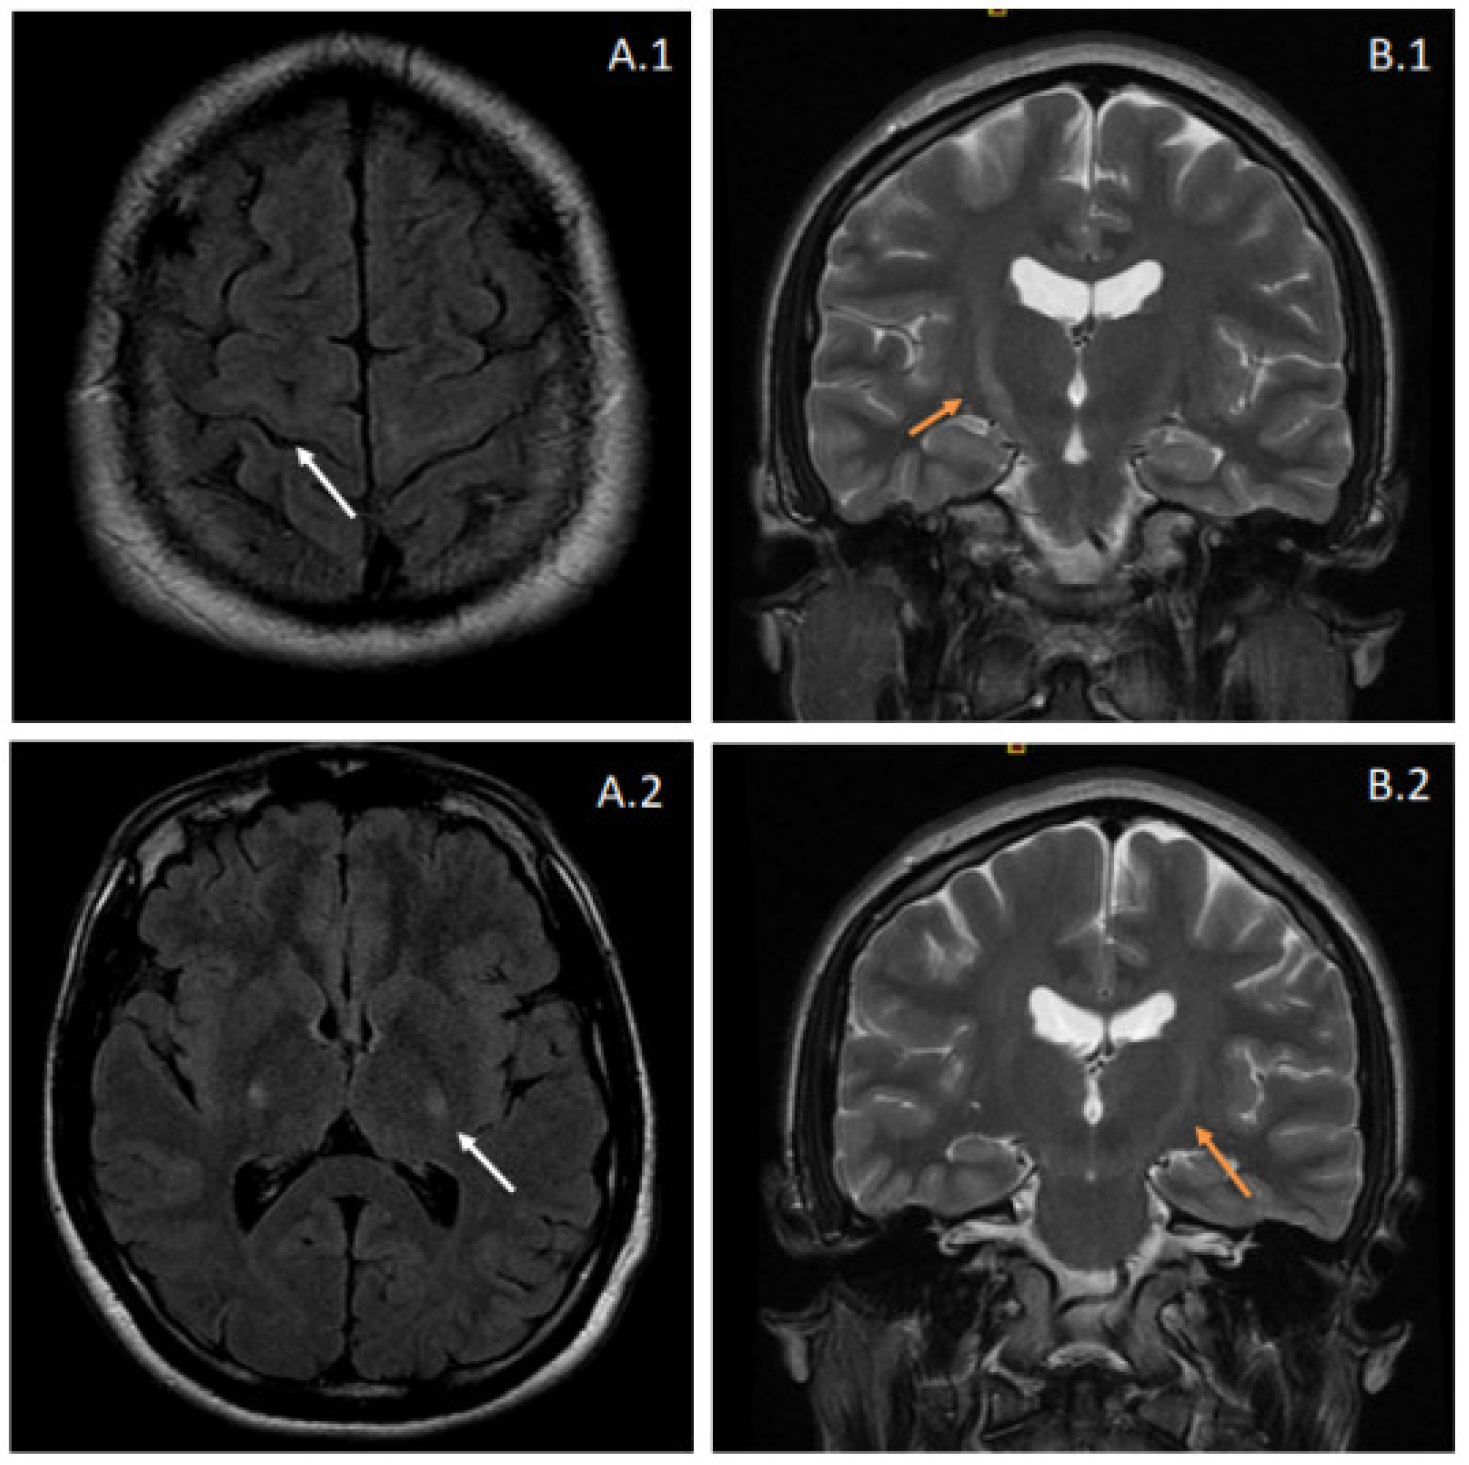

2.1. Clinical Presentation